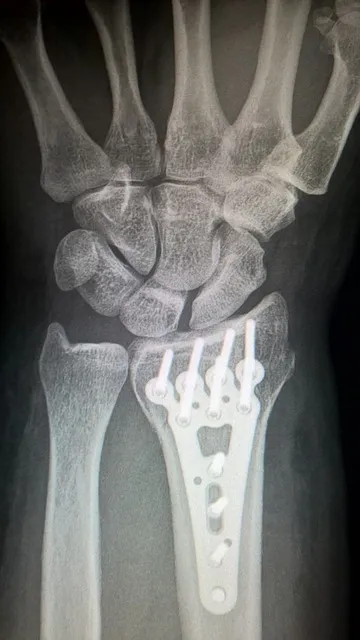

针对肩胛骨骨折的治疗,采取的方法有很多,主要视病情轻重而定。轻度骨折通常可以通过保守治疗来恢复,如使用止痛药、固定和休息等。然而,对于较严重的骨折,尤其是伴随其他复杂伤害时,可能需要手术治疗。

医生通常根据具体的病例选择适当的治疗方案,如通过X光、核磁共振等影像学检查确定骨折的具体情况。对于一些疼痛较为严重的患者,可以使用酮咯酸氨丁三醇注射液等药物进行止痛。中药的硬膏热贴敷治疗也是一种有效的辅助疗法,通过药物的外部作用缓解疼痛和促进血液循环。此外,患者还可以使用一些传统的中药,如盘龙七片、恒古骨伤愈合剂等,加速骨折的愈合过程。